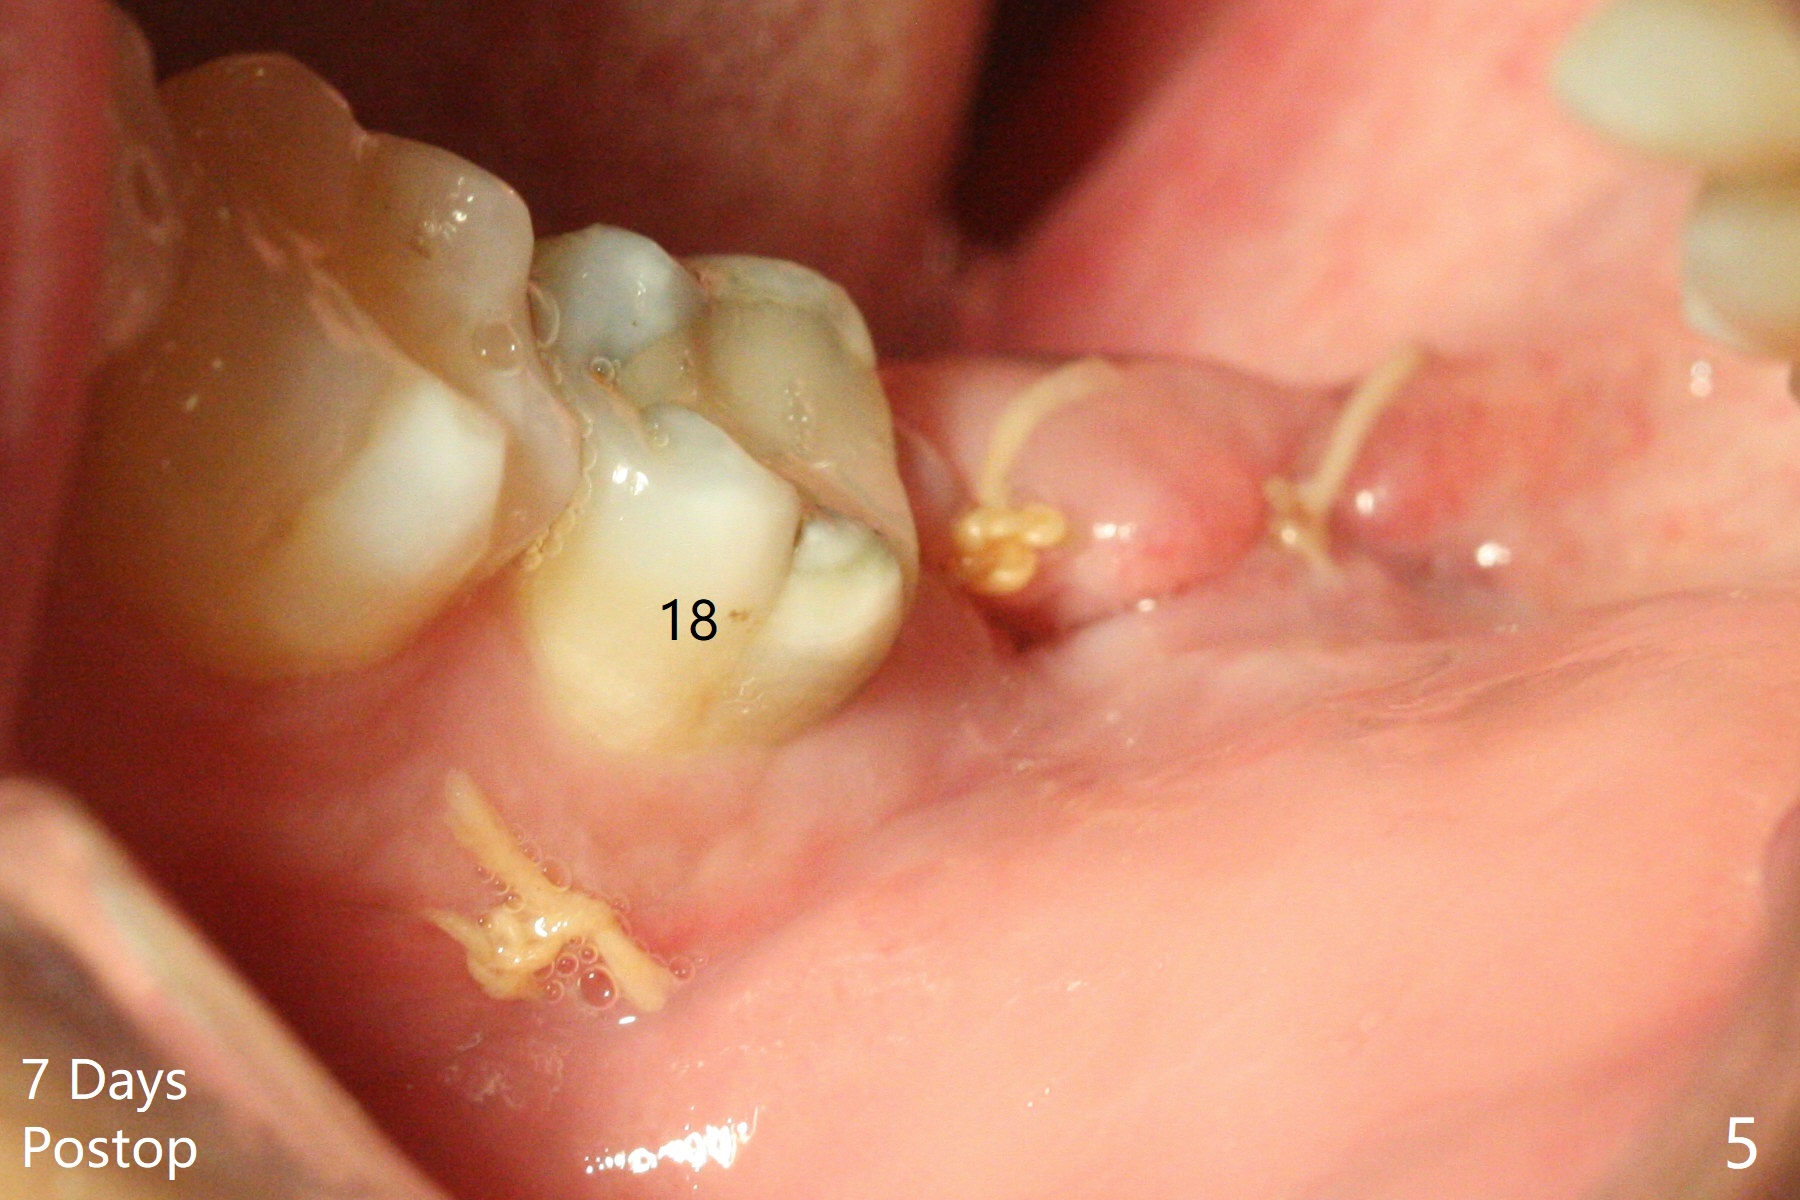

A 26-year-old man returns for #17,32 extraction 5.5 months post #1,16 one (Fig.1,2). In fact the crown/abutment at #31 is loose and removed, which makes easy for access, debridement with Titanium brush and bone graft (Fig.2 arrowheads, Ossogen). Osteogen plug is placed in the extraction sockets. The patient has limited mouth opening. Hemorrhage in #17 socket is controlled apparently with the plug following incomplete removal of granulation tissue. A piece of 12x12 mm Amnion-Chorion Membrane seems small for bone graft coverage. Cytoplast is added, followed by PGA suture. The former may keep the bone graft in place in case the wound dehisces. In fact the implant was not placed deep enough. It should have been removed. Although the wounds at #31/32 and 17 heal 7 days postop (Fig.3,5), the Cytoplast is visible immediately underneath the lingual gingiva at #31 (Fig.4 * (bulging)). The patient returns for Cytoplast (Fig.6 (occlusal view) *) removal 5 weeks postop. The procedure is done smoothly.